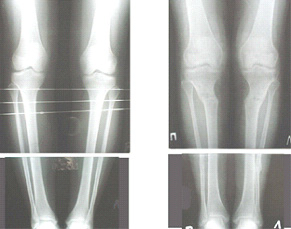

Картинки - в приложении.Будут вопросы - готов ответить.

Ещё картинка - схема. Хотя у Соломина всё написано.